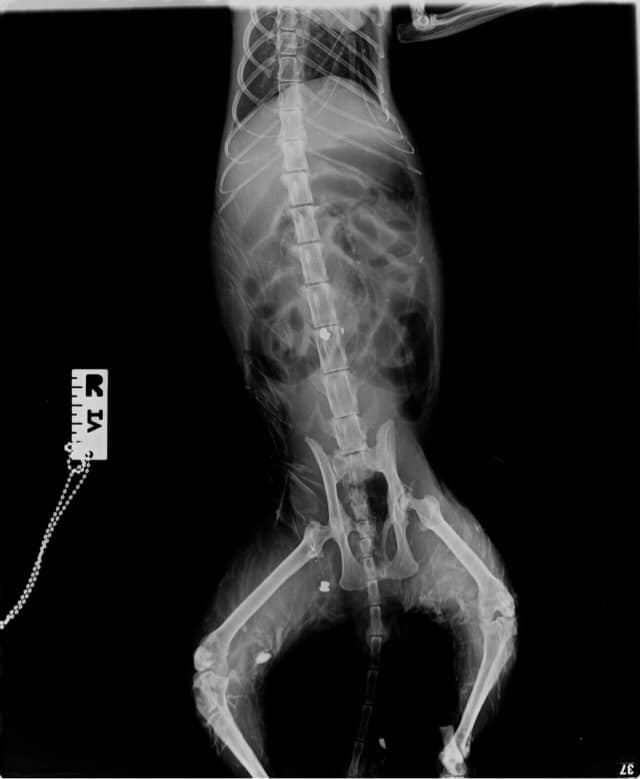

Ο γάτος μεταφέρθηκε άμεσα για πρώτες βοήθειες. Δυστυχώς στο κτηνιατρείο διαπιστώθηκε ότι ήταν πυροβολημένος πολλές φορές με αεροβόλο. Μετά τη λήψη ακτινογραφιών εντοπίστηκαν τρεις σφαίρες στο σώμα του, μια εκ των οποίων στη σπονδυλική στήλη.

Το ζώο νοσηλεύεται σε κρίσιμη κατάσταση λαμβάνοντας απαραίτητη φροντίδα και ορό στο κτηνιατρείο της κυρίας Λαγάνη. Είναι πλήρως αφυδατωμένος και με πολύ χαμηλό αιματοκρίτη.Γίνεται προσπάθεια, όπως αναφέρει η Alma Libre, συνεννοήσεων και επαφών με ορθοπεδικούς και νευροχειρουργούς προκειμένου να πραγματοποιηθεί σχετικό χειρουργείο, το οποίο θέλει εξειδικευμένο χειρισμό.